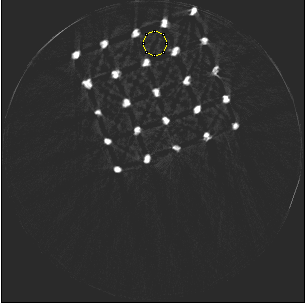

For the beam hardening study, we used Medipix All Resolution System (MARS) [12] containing a Medipix3RX ASIC with a 2 mm CdTe sensor bump bonded at 110 m in a single chip layout. All the acquisitions in this paper were carried out in CSM. The detector assembly is a module of the MARS camera which also contains a readout board, peltier cooling system and an integrated bias-voltage board. A negative bias voltage of -440 V was applied across the sensor during the acquisitions. The MARS scanner system comprises of MARS camera, a rotating internal gantry and an 80 kVp Source-Ray SB-80-1K x-ray tube (Source-Ray Inc, Ronkonkoma, NY) with a tungsten anode having 1.8 mm aluminium (Al) equivalent intrinsic filtration. The focal spot size is approximately 33 m [13]. Mechanical motor control (gantry rotation, source to detector translation, camera translation and sample translation), detector energy response calibration and threshold equalization were performed using the custom built MARS scanner software. The samples used in this study are shown in figure 2 and its description is provided in table 1.

| Sample | Material |

Description

|

|---|---|---|

| Metal phantom | Ti alloy | Solid cylinder of 8 mm diameter press fitted onto a Perspex cylinder of 25 mm diameter to study cupping effect. |

| Porous scaffold | Ti alloy | Porous 3D lattice structure fabricated via electron beam melting with 700 m thick struts. Used in tissue engineering research. |

| Porous scaffold | Mg alloy | Porous 3D lattice structure fabricated via an indirect additive manufacturing process in molten Mg with 500 m thick struts. Used in tissue engineering research [9]. |

| Porous mesh (stent-like pattern) | Ti alloy | Porous 3D structure fabricated via selective laser sintering with variable strut thickness between 620 m and 670 m. Sample length measures 45 mm (includes a 10 mm base). |